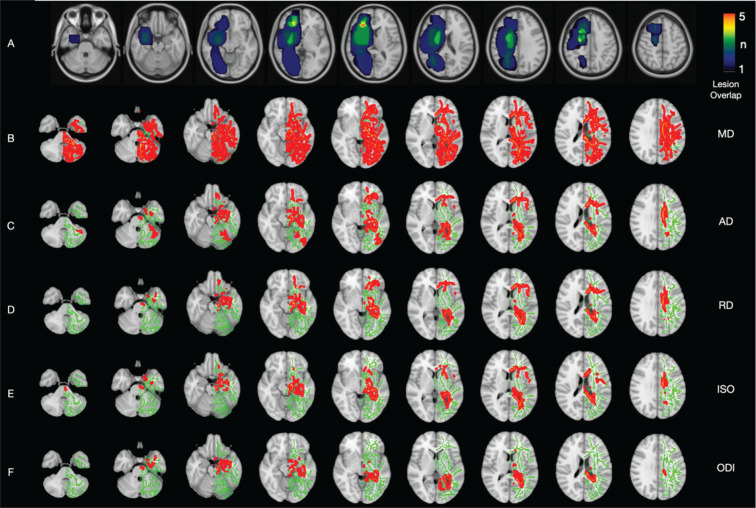

Methods: Fourteen right-sided and eleven left-sided glioblastoma patients without any treatment and eighteen age- and gender-matched controls were included in the study. Multi-shell diffusion weighted images were created with a 3T MRI device. After various preprocessing steps, images of fractional anisotropy (FA), mean diffusivity (MD), axial diffusivity (AD), radial diffusivity (RD), axial kurtosis (AK), mean kurtosis (MK), radial kurtosis (RK), intracellular volume fraction (ICVF), orientation dispersion index (ODI), and isotropic water fraction (ISO) were obtained. TBSS was used to compare diffusion tensor imaging, diffusion kurtosis imaging, and neurite orientation dispersion and density imaging parameters of right- and left-sided glioblastoma patients with the control group for the contralateral hemisphere.

Results: Both right-sided and left-sided glioblastoma patients have shown an increase in MD and ODI in the contralateral hemisphere. While right-sided glioblastoma patients showed an increase in RD, AD, and ISO in a more limited area in the contralateral hemisphere, left-sided glioblastoma patients showed an increase in MK and AK. FA, ICVF, and RK did not show any difference in both groups.